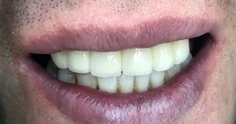

어쨌든 결과적으로

요렇게

아래 앞니 지르코니아 브릿지와

윗니는 PFM 브릿지

(지금 보이는 이 중에 위 앞니는 3개는 없는 상태

아래 앞니는 2개가 없는 상태입니다.

없는 치아5개포함 지금 보이는 이 중 총10개가 가짜)

하셨습니다.

환자분이 이도 원래이 보다 고르게 되고 하얗게 되고 아주 엘레강스 해졌다고

아주아주 좋아하셨습니다.

성형을 해주는 치과라며 칭찬하셨어요.